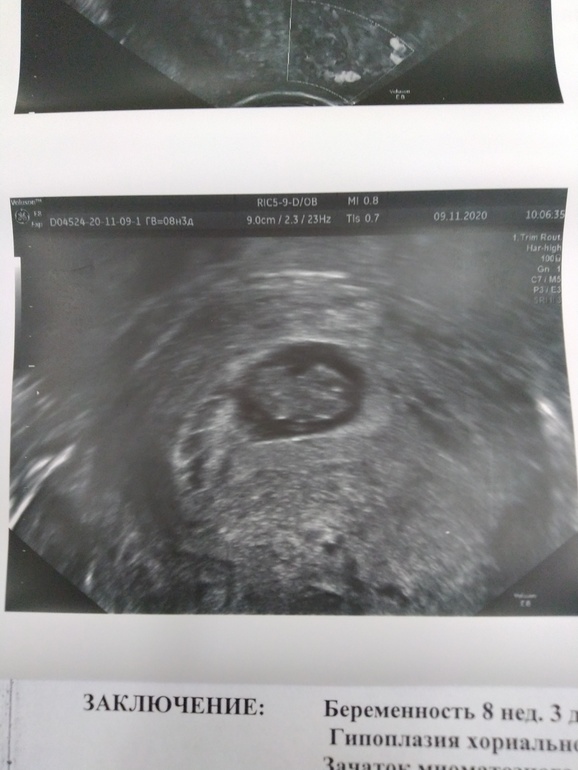

Гипоплазия хоральной полости

Замершая и внематочная беременностьКто может объяснить что это? Срок 8нед +3 дн. Шансы есть или ничего хорошего не сулит?

Надо смотреть, это длина или диаметр

В общем надо просто смотреть по узи насколько тесно там эмбриону

Если это длина,то плохо. Тк эмбриону только 1.4 мм для роста. Но шансы в любом случае есть.

Тесновато, конечно.

Но не критично, место пока есть. Лишь бы росло пя

До 11-12 нед надо продержаться. Дальше эмбрион начнёт писать и сам сделает себе амниотический пузырь